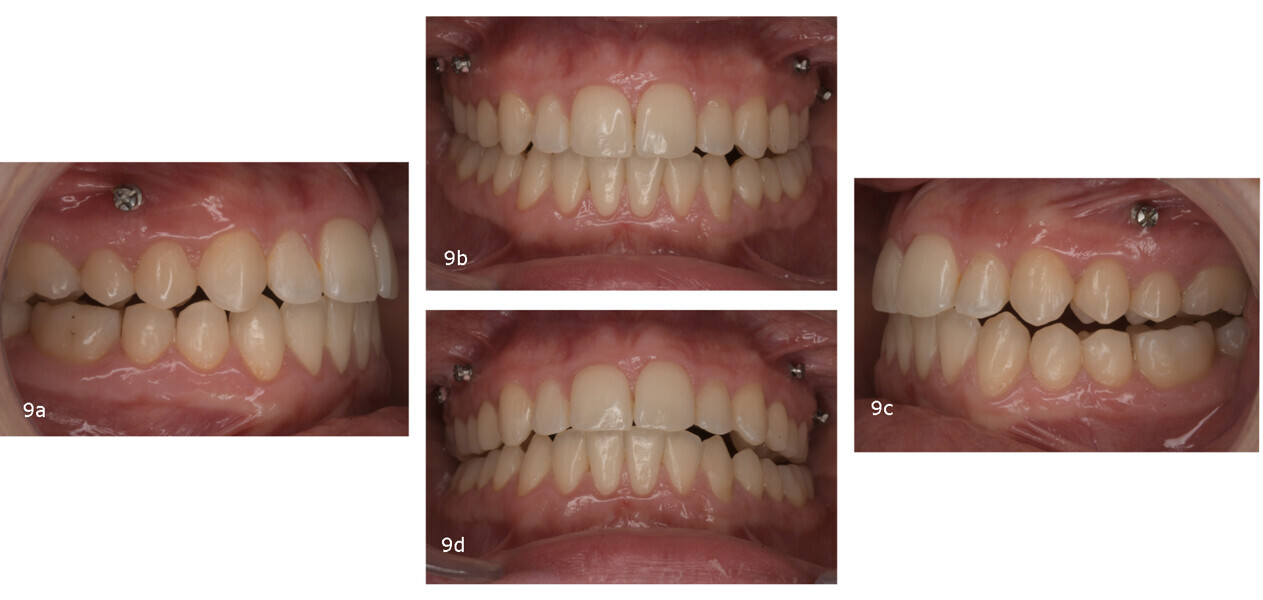

After the reset phase, which involved treatment with 12 aligner pairs, treatment continued with a focus on further maxillary posterior intrusion to fine-tune the vertical correction (Fig. 9). The second round of aligners targeted case finishing with the specific objectives of improving posterior intercuspation, achieving precise midline correction and enhancing sagittal relationships through posterior IPR and the bilateral use of Class III elastics (Fig. 10).

Final outcomes

After 18 months of treatment, including the reset phase and refinements, the patient exhibited significant extra-oral improvements, including a more harmonious smile arc, increased incisor display at rest and notable facial profile enhancement driven by effective mandibular auto-rotation (Fig. 11). Intra-orally, the results included Class I molar and canine relationships, proper alignment and levelling of both arches, an ideal overjet and overbite, and coinciding maxillary and mandibular midlines (Fig. 12).